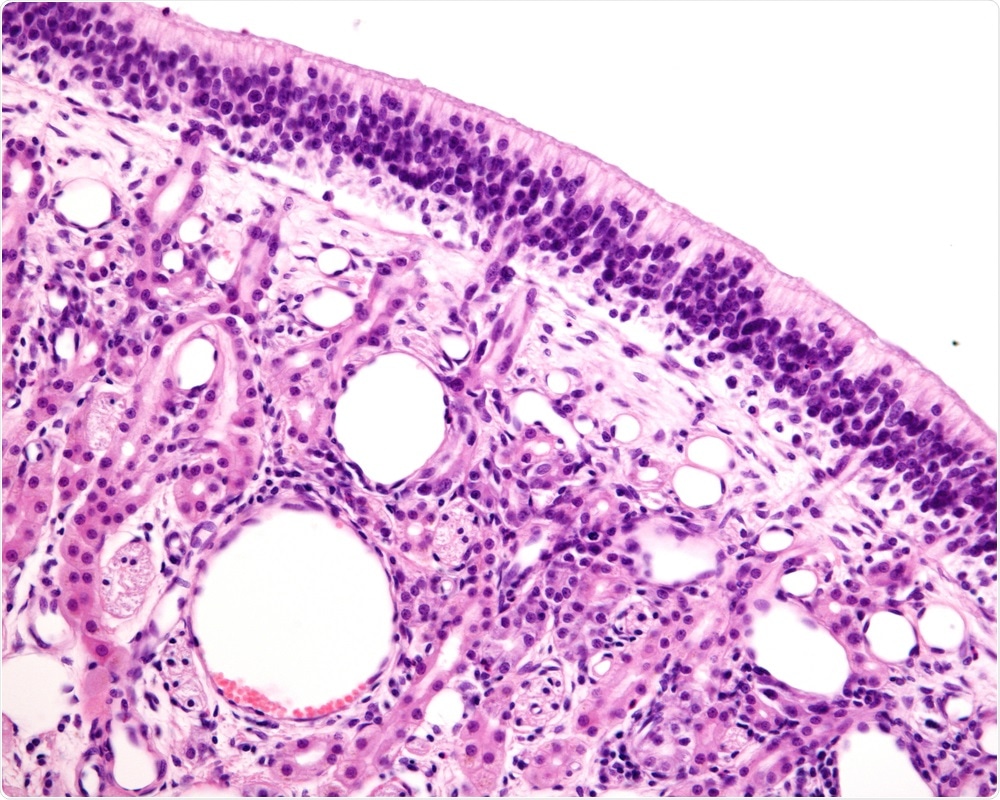

In these cases, if you carry out microscopic studies of the tissue, you can see that the virus has damaged the structure of the receptor cells.

Typically, you will see that the fine hair endings that dangle down into the mucus have dropped away, therefore the cells cannot pick up any smells from the nasal mucus.

Image Credit: Jose Luis Calvo/Shutterstock.com